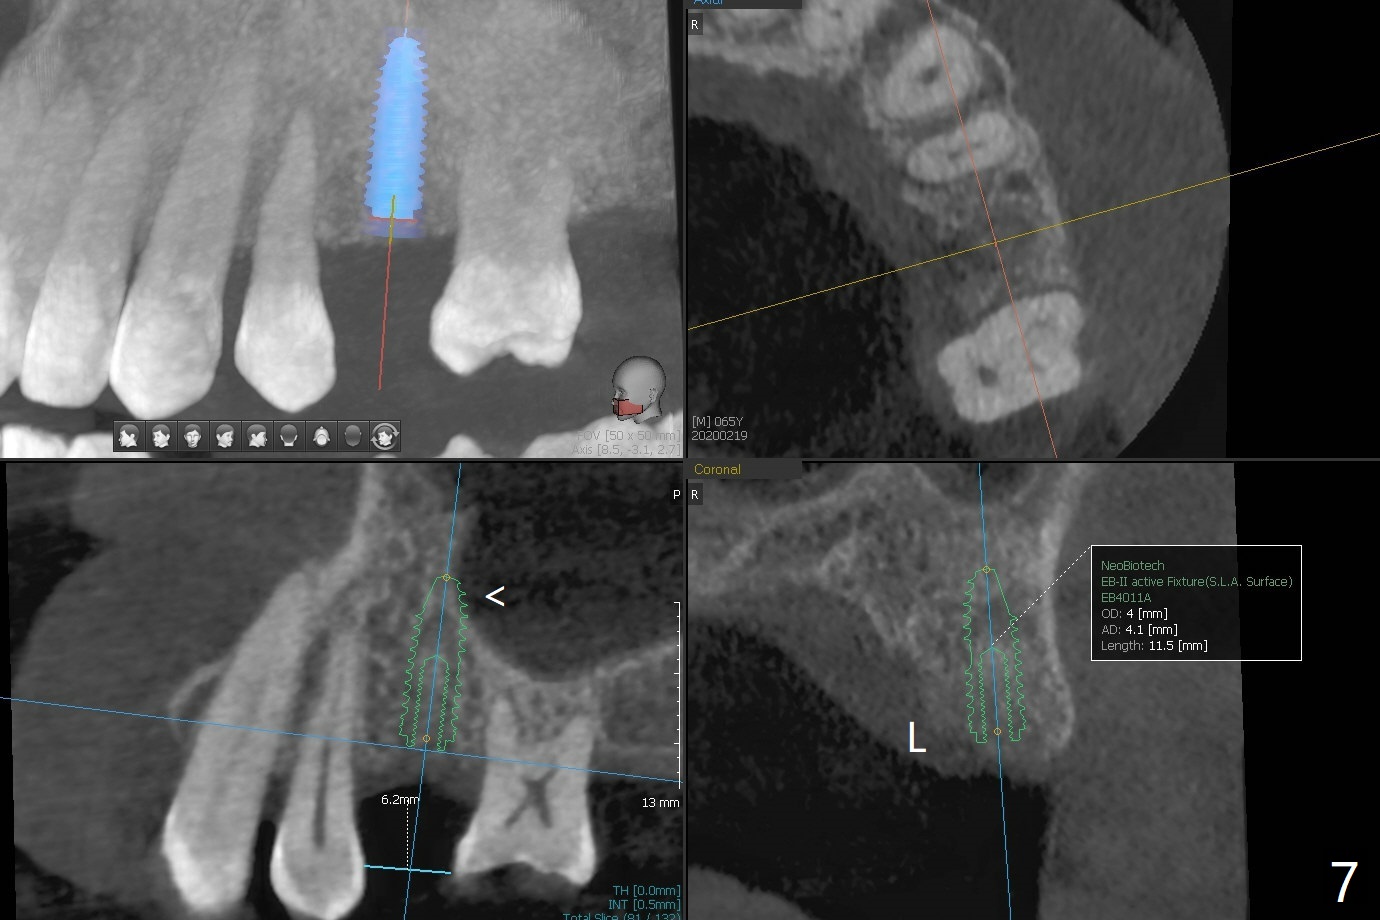

A 65-year-old man cracks 3 teeth in ~2 years (Fig.1,2 (#4,13,15)). The tooth #4 is symptomatic after RCT (Fig.1); it appears that the buccal canal is incompletely filled (data not shown). In fact an exam 1 month later shows that the symptomatic tooth is #2 (crack), while #4 is salvageable (Fig.8). The tooth #13 has palatal subgingival fracture with severe pain (Fig.2 with palatal defect). In fact the title of this case is incorrect). After extraction, allograft is placed (Fig.3 *) with 6-month membrane. In fact the bone graft is not packed into the apex of the socket; a condenser should have been used. The patient returns 3 days postop before leaving abroad. The 6-month membrane remains in place (Fig.4), while the ridge at #15 is minimally atrophic (Fig.5). The coronal lamina dura becomes indistinct 5 months postop (Fig.6). The bone graft remains in the socket. The distoapical portion of a 4x11.5 mm implant may be in the sinus (Fig.7).